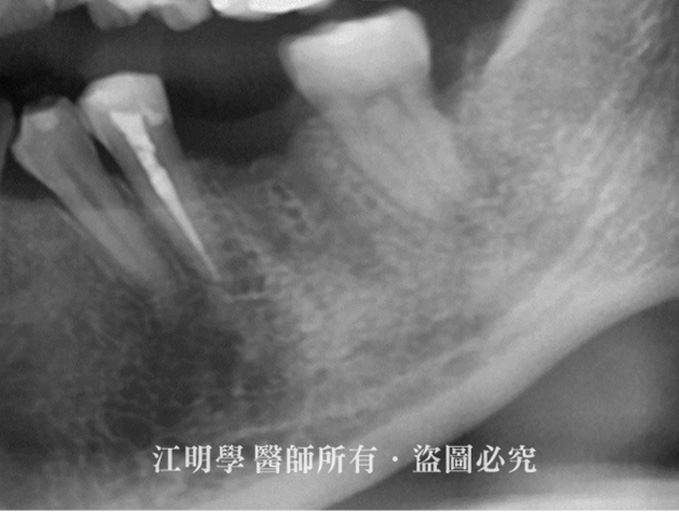

治療前:大臼齒缺牙

治療前X光